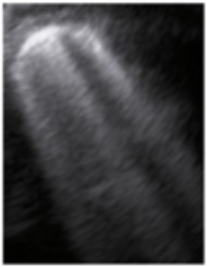

- Subpleural consolidation <1 cm (Figure 4a,b)—31.57%;

Figure 4. (a) The lung ultrasound showed a small consolidation area with the length <1 cm corresponding to a LUSS = 2; (b) The CT exam revealed bilateral consolidations in the posterior segments. - Pleural effusion—5.26%.